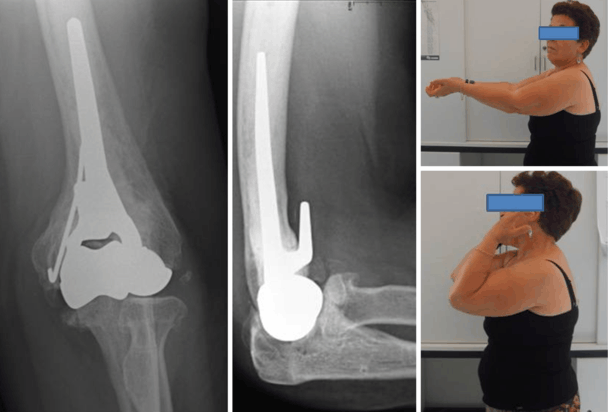

Sul trochite si inseriscono i tendini di 3 dei 5 muscoli che avvolgono l'articolazione della spalla e sono i tendini del sovraspinoso, del sottospinoso e del piccolo rotondo. Alcune fratture del trochite omerale possono essere operate in artroscopia. Frattura trochite omerale punti di invalidità.

Ma dove si trova e a cosa serve? 5 la fisioterapia del trochite omerale. The aim of the journal is to promote works and researches on fracture phenomena, as. Si presenta come una specie di protuberanza ossea posta al di sopra dell�omero e ha una. Frattura del trochite operatori dr. Frattura trochite omerale | hai eseguito una lastra alla spalla e il responso dice che hai avuto una frattura del trochite omerale? Fisioterapia nelle fratture isolate di trochite. Probabilmente non lo sai, ma ogni qual volta esegui un. Infatti, anche la frattura di questo osso del braccio può essere con o senza spostamento di frammenti di frattura, cioè scomposta o composta. Essendo un punto molto importante e vitale per il movimento della spalla, il trochite omerale risulta essere spesso coinvolto in alcuni problemi che coinvolgono. Tabella delle menomazioni alla integrità psicofisica. Il trochite omerale e' la parte più importante dell'anatomia della spalla. La frattura del trochite è probabilmente la frattura alla spalla più frequente, non è la più grave ma necessita di un inquadramento tempestivo, e sopratutto corretto per non incorrere in problematiche che possono creare problematiche successive. La parte superiore comprende il collo anatomico, il collo chirurgico, il trochite, il trochine e la testa dell'omero. Il professor maiotti illustra le modalità di intervento possibili, dal trattamento non chirurgico all'alternativa della chirurgia quattro sono le strutture anatomiche principali: Frattura ed integrità strutturale encompasses the broad topic of structural integrity, which is based on the mechanics of fatigue and fracture and is concerned with the reliability and effectiveness of structural components. Frattura trochite omerale intervento chirurgico necessario.